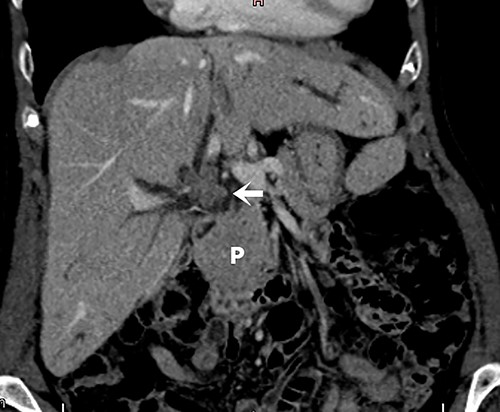

Screening for staging was performed, with ultrasound of the abdomen showing a suspicious neoplasia at the common hepatic duct. Cholangioresonance findings were suggestive of cholangiocarcinoma (Fig. 1). Computed tomography (CT) demonstrated a solid and irregular nodule (Fig. 2).

Abdominal tomography with intravenous contrast enhancement showing a solid and irregular nodule (white arrow) that caused retraction of the gallbladder bed and loss of the cleavage plane with the proper hepatic artery and portal vein, measuring 30 × 26 × 27 mm. The lesion is invading the biliary tract at the confluence of the hepatic ducts. There are no evident vascular invasion and no regional lymph node enlargement. The pancreas (P) is normal.